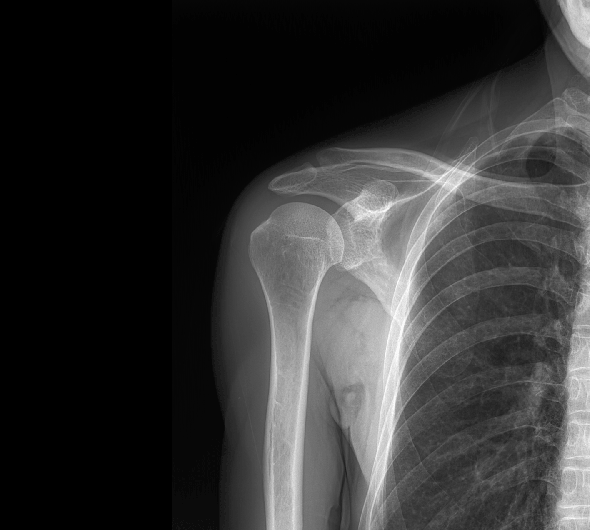

原厂优质影像链,搭载直接生长式碘化铯非晶硅平板,带来更加清晰锐利的图像效果。